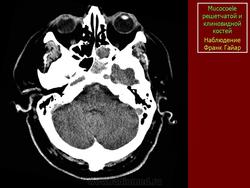

Мукоцеле

Приложения:

1.mu_.slayd364.jpg2.mu_.slayd365.jpg3.mu_.slayd366.jpg